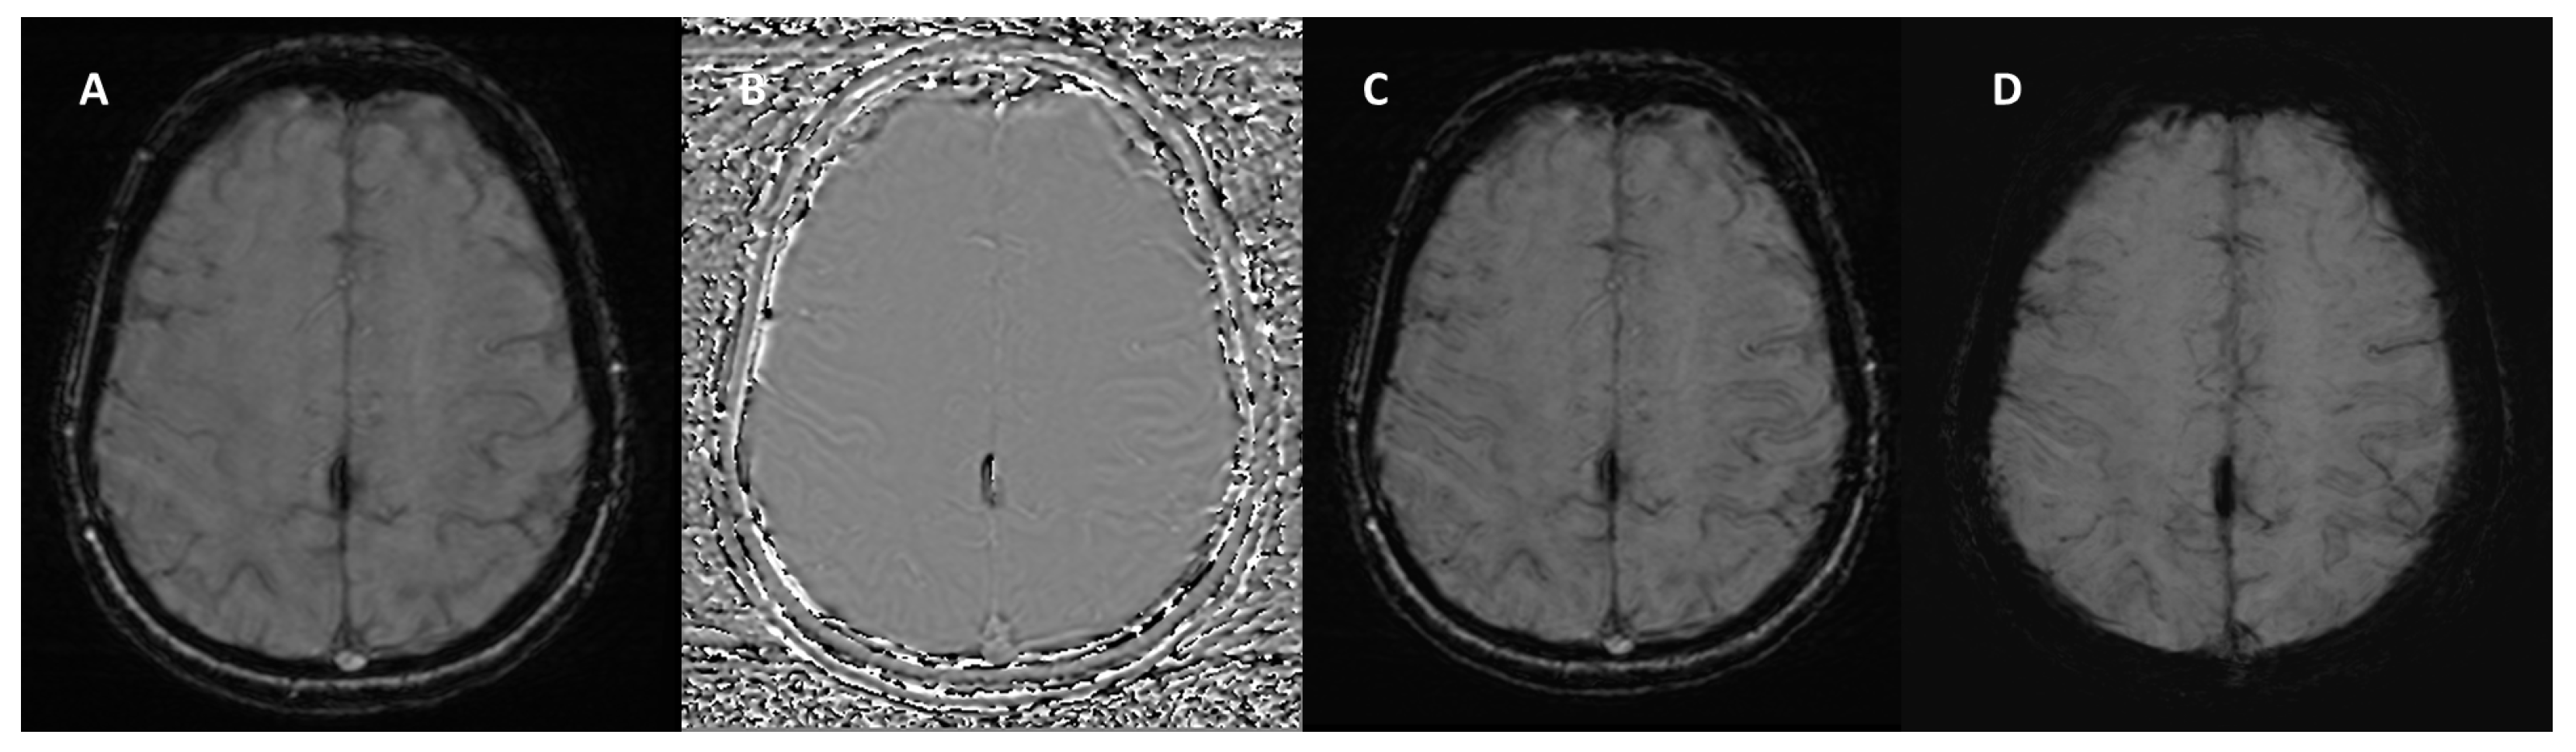

3. Technical Fundamentals of SWI